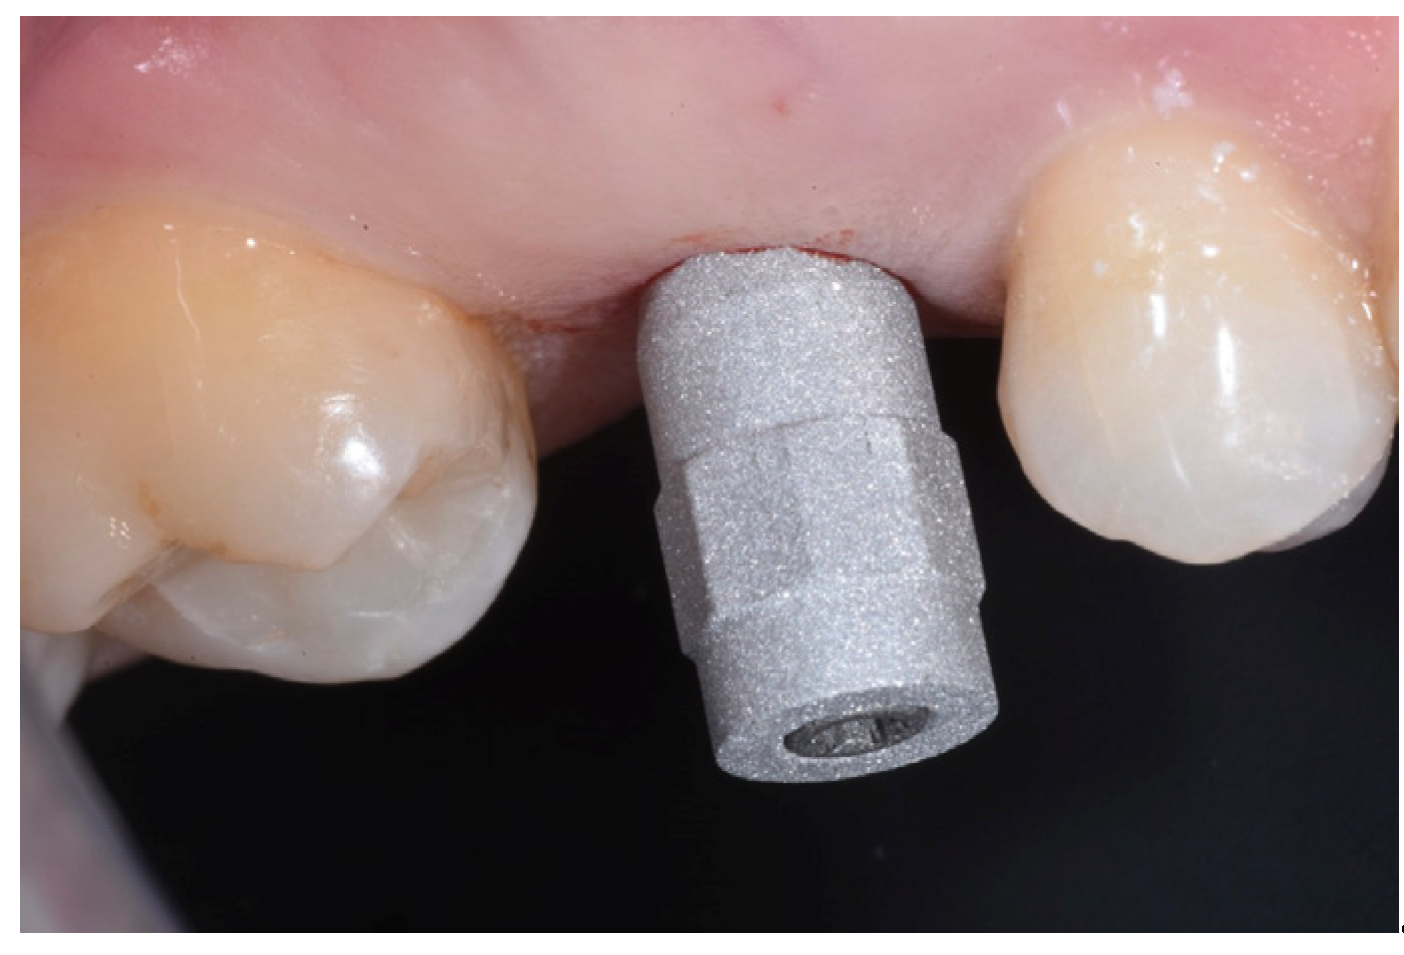

2.6. Case Presentation. Nano-HA Applied to Socket Preservation Procedures

3. Results